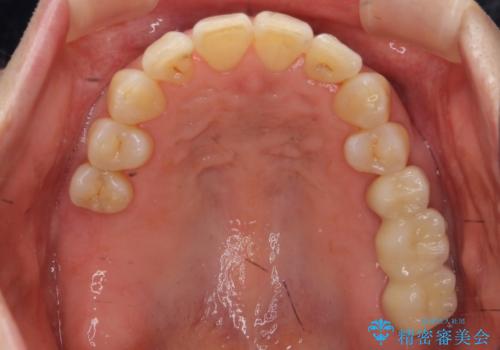

前歯が反対になっている マウスピース矯正+奥歯ブリッジ

- 前歯のがたつきを主訴に来院。

奥歯も少なく、左上奥歯はブリッジにすることになりました。

- 140.8万円(矯正治療:104.5万円、奥歯ブリッジ:36.3万円[ジルコニアクラウン10万円x3 仮歯x1万円x3])費用は治療当時の料金となります

右上大臼歯2本の欠損については、インプラント治療をお勧めしましたが、ご希望によりそのままとなりました。